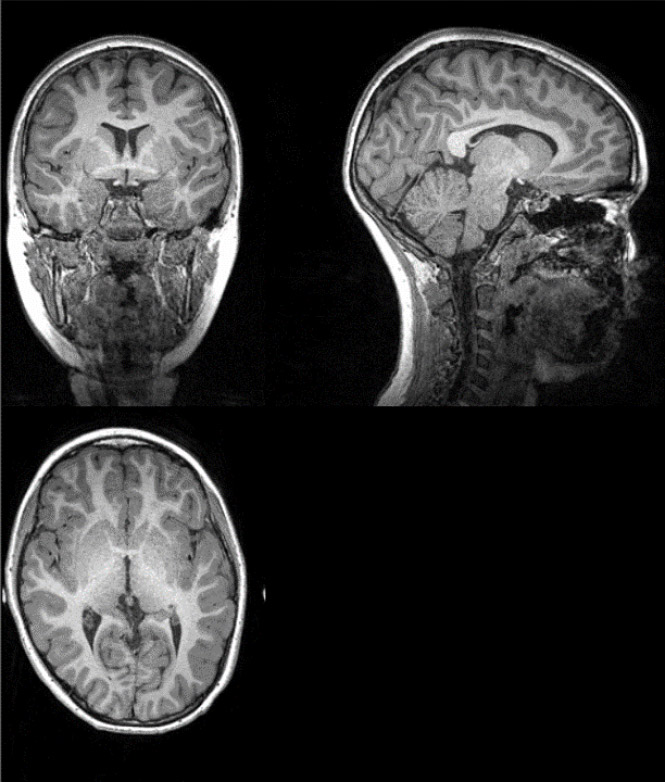

Los niños que tienen mejor forma física tienen cerebros más grandes, y tanto la capacidad aeróbica como la fuerza o la velocidad están relacionadas con la cantidad de materia gris y blanca del cerebro en niños con sobrepeso u obesidad. Además, una mayor cantidad de materia blanca en el cerebro está relacionada con un mayor rendimiento cognitivo.

Este trabajo, publicado en la revista Scandinavian Journal of Medicine &Science in Sports, revela que los niños que fueron clasificados como “en forma” tenían mayor cantidad de materia gris, materia blanca, y en general, cerebros más grandes que aquellos niños que fueron agrupados como “en baja forma”. Asimismo, tener más materia blanca en el cerebro estaba relacionado con un mayor rendimiento cognitivo, concretamente, mayor flexibilidad cognitiva y función ejecutiva.